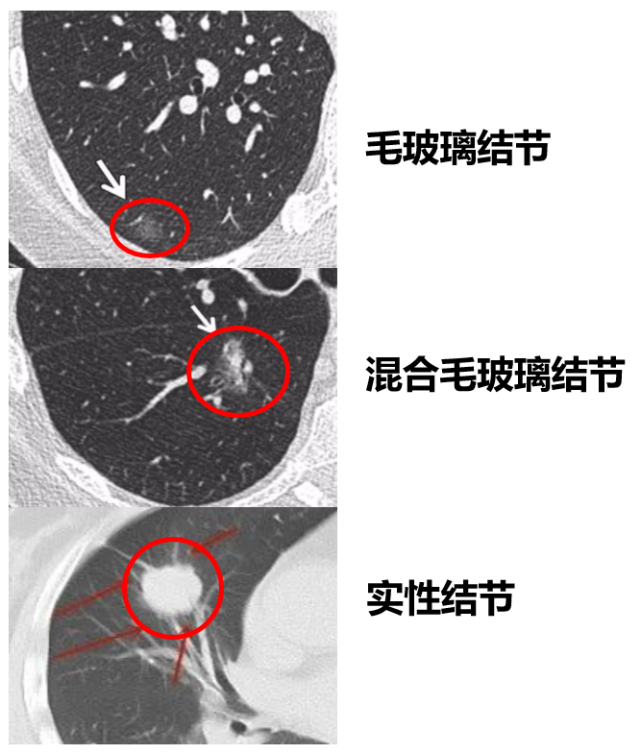

这类肺腺癌,可能表现为毛玻璃结节,或混合毛玻璃结节,或实性结节

这都是常见的表现形式,也很好判断。

图片